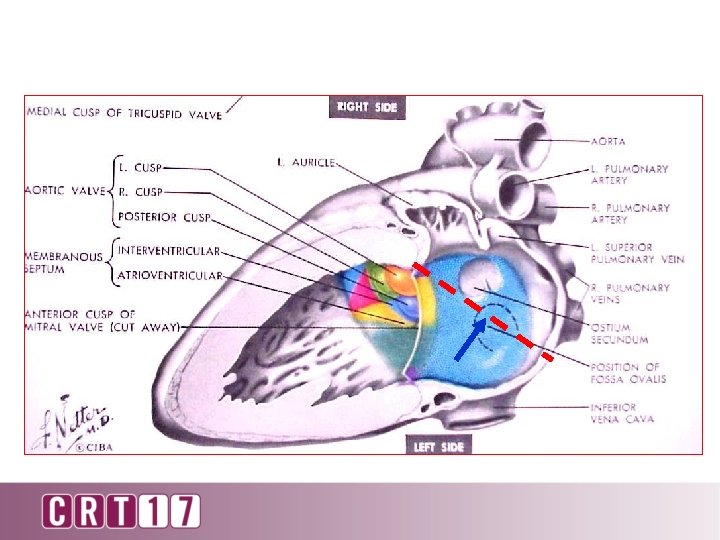

90 o lateral

90 degree lateral

Puncture high and posterior Puncture low and posterior